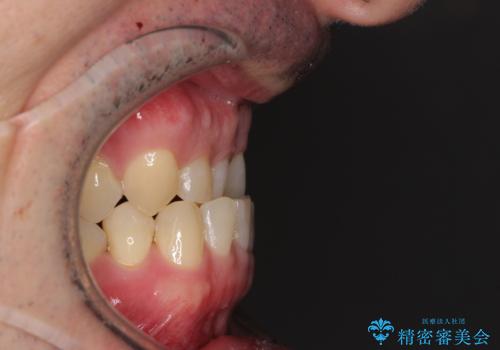

受け口を治す ワイヤー装置での矯正治療

- 上下前歯の反対咬合と左下奥歯の痛みを気にして来院された患者様です。

歯並びや口元の印象、奥歯の咬み合わせから、非抜歯にて矯正治療を行うこととしました。

インプラント埋入による仮歯の装着や、前歯の反対咬合の改善は比較的スムーズに達成されましたが、舌突出癖などの影響による、歯列全体のスペースを閉じることが難航し、期間がかかってしまいました。